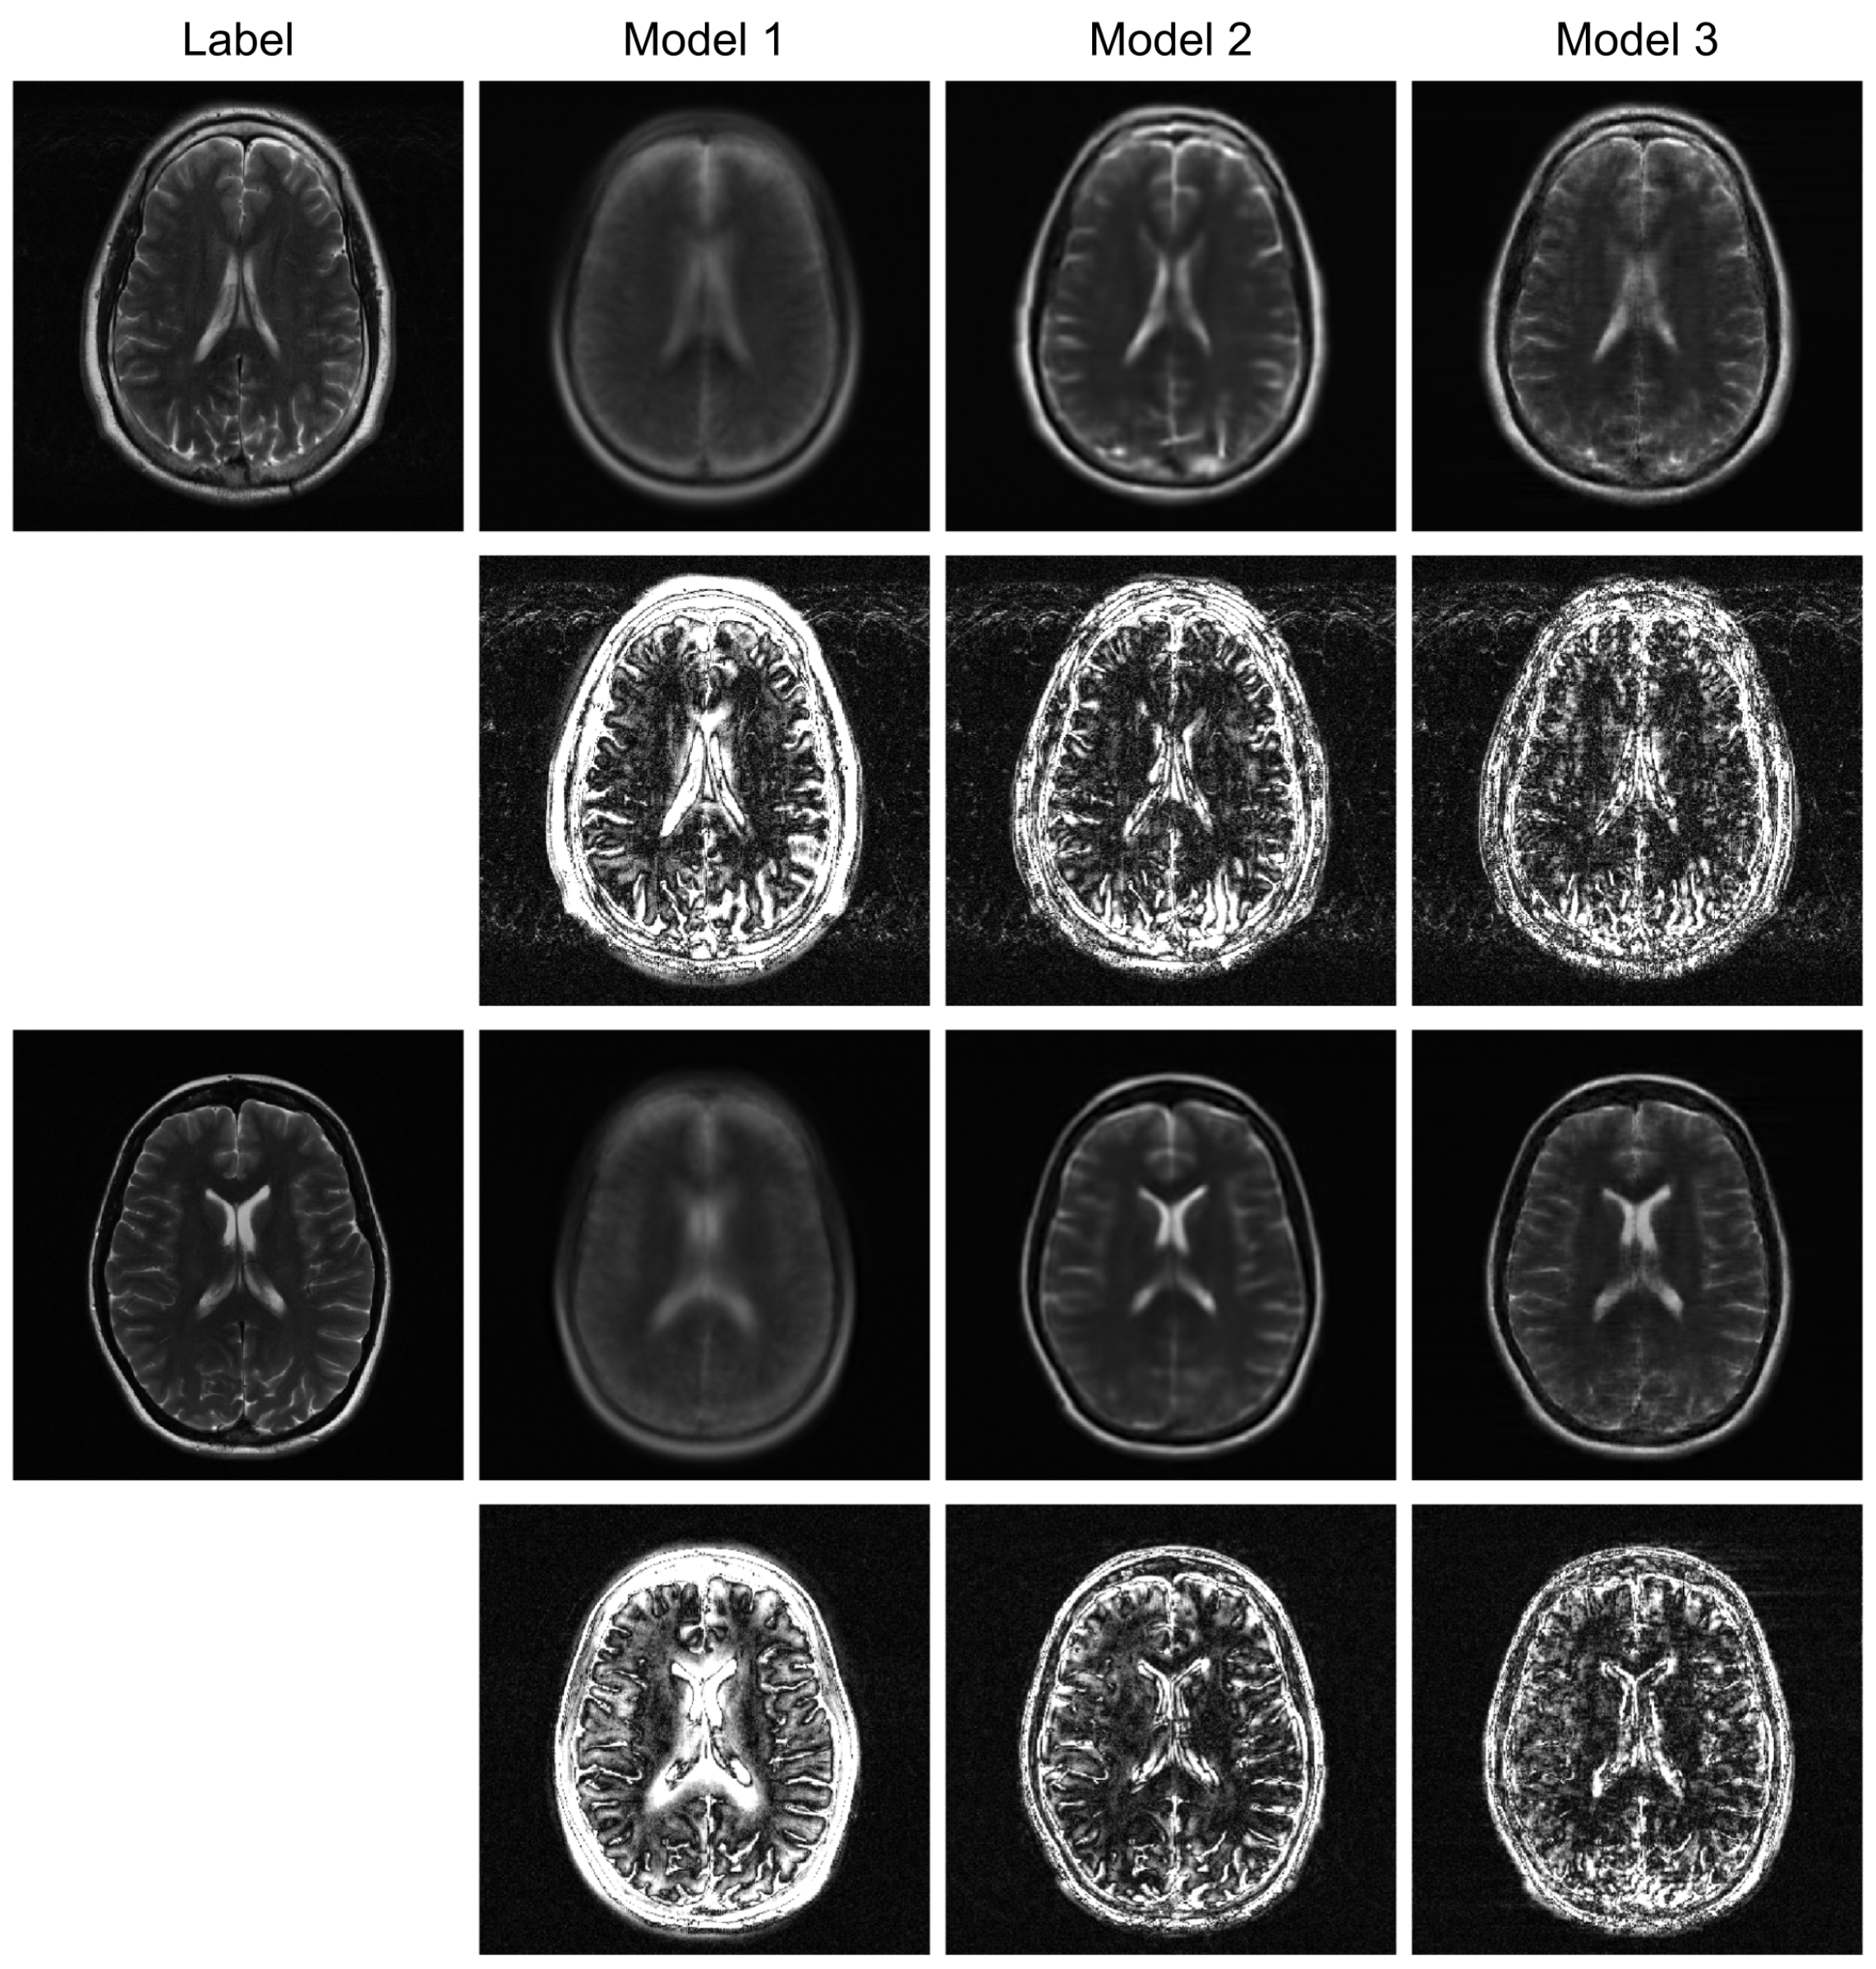

To further evaluate the robustness of our proposed model, we conducted additional experiments under higher acceleration factors (R = 8) and with different undersampling patterns (regular and random). For the random sampling scenarios, a new undersampling mask was randomly generated for each sample, which prevents the model from overfitting to a fixed pattern and enhances generalization. The qualitative results are presented in Figure 3, Figure 4 and Figure 5, and the corresponding quantitative analysis is summarized in Table 1. At a higher acceleration factor of R = 8 (Figure 4 and Figure 5), the performance gap between the models becomes more pronounced. While all models exhibit increased artifacts compared to R = 4, Model 3 consistently preserves anatomical structures more effectively than the other models, particularly in the more challenging random sampling scenario (Figure 5). The quantitative results in Table 1 align with the visual assessment. Across all tested scenarios—R4 random, R8 regular, and R8 random—Model 3 consistently achieves the lowest nMSE and the highest SSIM and VIF scores.

The comparison between Model 2 and Model 3 effectively serves as an ablation study, isolating the contribution of the BiRNN module. The significant performance improvement observed in Model 3, particularly under high acceleration (R = 8) and random sampling conditions (Table 2), underscores the critical role of processing k-space data directly. While the Transformer decoder in Model 2 can reconstruct global structures from the encoder’s latent features, it struggles with the complex, non-local aliasing artifacts inherent in undersampled data. The BiRNN module in Model 3 addresses this by interpreting k-space as sequential data, effectively capturing the structured correlations along the phase-encoding directions. This allows the model to disentangle aliasing patterns from true anatomical features before the final fusion step, resulting in superior artifact suppression and detail preservation, as visually confirmed in Figure 4 and Figure 5.

Furthermore, the model’s robustness against different sampling patterns demonstrates its generalization capabilities. The regular sampling pattern (Figure 5) produces coherent, line-like artifacts, whereas the random pattern (Figure 4 and Figure 6) generates more incoherent, noise-like artifacts. Model 3’s consistent high performance in both scenarios indicates that the hybrid architecture, which processes global image-domain context via the ViT and models frequency-domain sequential dependencies via BiRNNs, achieves high adaptability to varying artifact structures. This adaptability is a significant advantage over methods optimized for only a specific type of artifact texture.

Figure 5. High-acceleration (R = 8) reconstruction with a regular sampling mask. The visual results and corresponding error maps (10× amplification) illustrate each model’s effectiveness in handling coherent aliasing.

Figure 6. Robustness test under a high-acceleration (R = 8) random sampling condition. The reconstructed images and their error maps (10× amplification) demonstrate performance degradation and artifact patterns in a highly incoherent scenario.